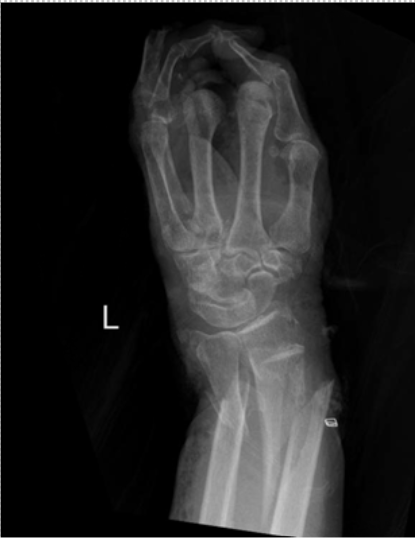

Figure 10. X-ray of the left hand of case 2.

Upon arrival, she received a tetanus shot and was placed on cefepime, vancomycin, and metronidazole. Grossly, there was extensive soft tissue damage to the left forearm and hand, in addition to exposed metacarpal bones and complete amputation of the index, long, and ring fingers on the left hand. Radiographs of the wrist demonstrated a comminuted open distal ulna and a comminuted articular distal radius fracture. Moreover, the left radial and ulnar arteries signals were lost distal to the site of the wrist fracture, and the distal tissue was cold to the touch. Computed tomography scan demonstrated a Morel-Lavallée lesion on her left thigh (Figure 11).